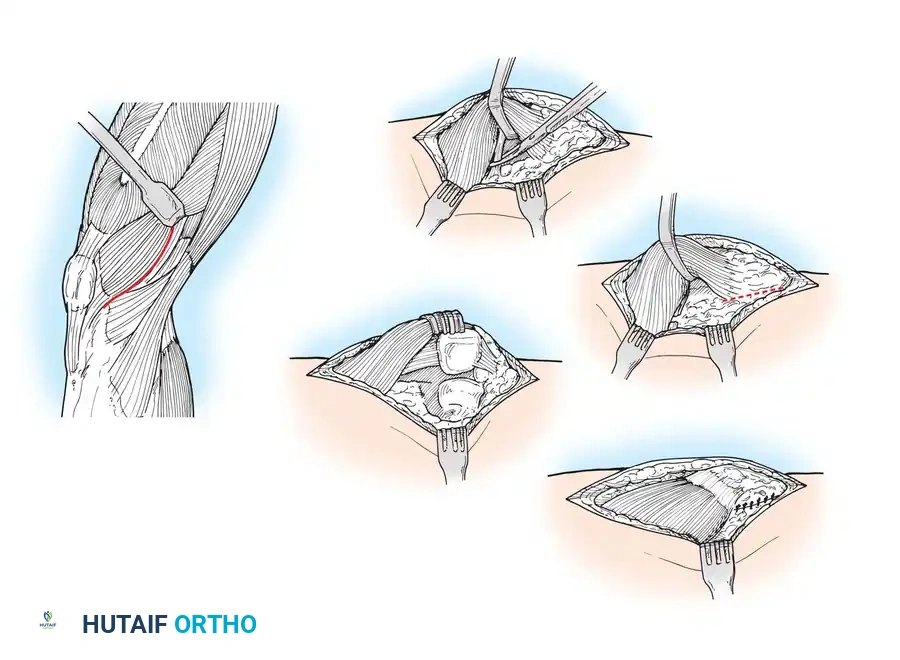

Initial Joint Preparation and Soft Tissue Management

Once the joint is exposed, systematic preparation of the intra-articular structures is required before bone resection.

- Flex the knee and excise the anterior cruciate ligament (ACL) and the anterior horns of the medial and lateral menisci.

- Remove any prominent osteophytes (especially in the intercondylar notch and medial/lateral gutters) that may lead to component malposition, impinge on soft tissues, or create artificial soft-tissue tension.

- The posterior horns of the menisci are often easier to excise after the initial femoral and tibial bone cuts have been made.

- If a Posterior Cruciate Ligament (PCL)-substituting (Posterior Stabilized, PS) prosthesis is planned, the PCL can be resected now or removed later during the intercondylar box cut.

- With both PCL-substituting and PCL-retaining procedures, subluxate and externally rotate the tibia. External rotation relaxes the extensor mechanism, decreases the risk of patellar tendon avulsion, and dramatically improves exposure of the lateral compartment.

- Expose the lateral tibial plateau by partially excising the infrapatellar fat pad and carefully placing a levering-type retractor adjacent to the lateral tibial plateau.